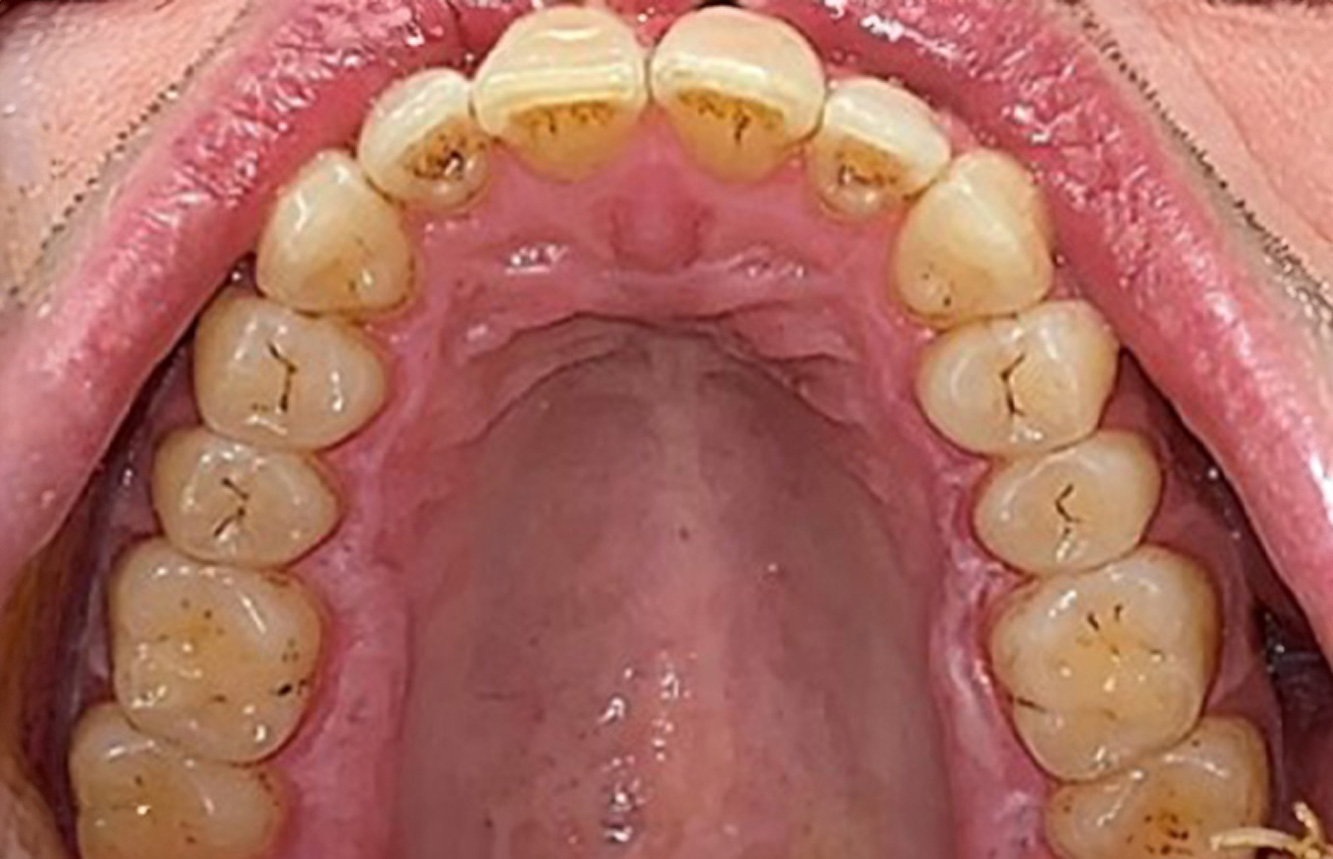

Ein 71-jähriger Patient mit Z.n. Nierentransplantation und Hypertonie (Bluthochdruck) stellt sich vor. Bedingt durch die Krankengeschichte ist eine Dauermedikation mit Cyclosporin, zur Unterdrückung der Immunabwehr, und Amlodipin, zur Blutdrucksenkung, erforderlich. Außerdem berichtet der Patient über empfindliches Zahnfleisch und Zahnfleischbluten. Aus mundgesundheitlicher Sicht zeigt sich ein saniertes Gebiss mit acht fehlenden Zähnen, ausgeprägte Gingivawucherungen, eine Parodontitis Stadium II, Grad B mit aktiven Taschen und eine initiale Wurzelkaries an Zahn 22. In der Kariesrisikoabschätzung wird ein mittleres Kariesrisiko (API 60) festgestellt. Für die Prophylaxesitzung lassen sich folgende Behandlungsempfehlungen ableiten. mehr Infos